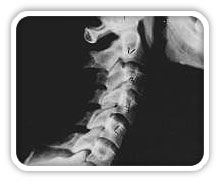

Near Normal

This is a side x-ray view of the neck. As with all the pictures you will see on this page, the patient is looking to the right of the screen, so you are viewing the right side of their neck. We will call this picture a "near normal" spine. Compare this spine with the ones you will see below on this page. Notice the normal forward curve of the neck. This curve helps absorb shock. Notice how each of the disc spaces between C2 (second bone in neck) and C7 are thick and even, this again is normal. Also notice how the front portions (right on the x-ray) of each of the vertebrae (called the 'body' of the vertebrae) are fairly square with clear and well defined borders. This type of arrangement is normal in the neck. Normal vertebrae in other parts of the spine also have similar characteristics to what we see here. When subluxations occur and are left uncorrected, ongoing relentless changes occur that result in damage to the structure and function of the spine along with nerve damage and the resulting problems caused from improper nerve supply.